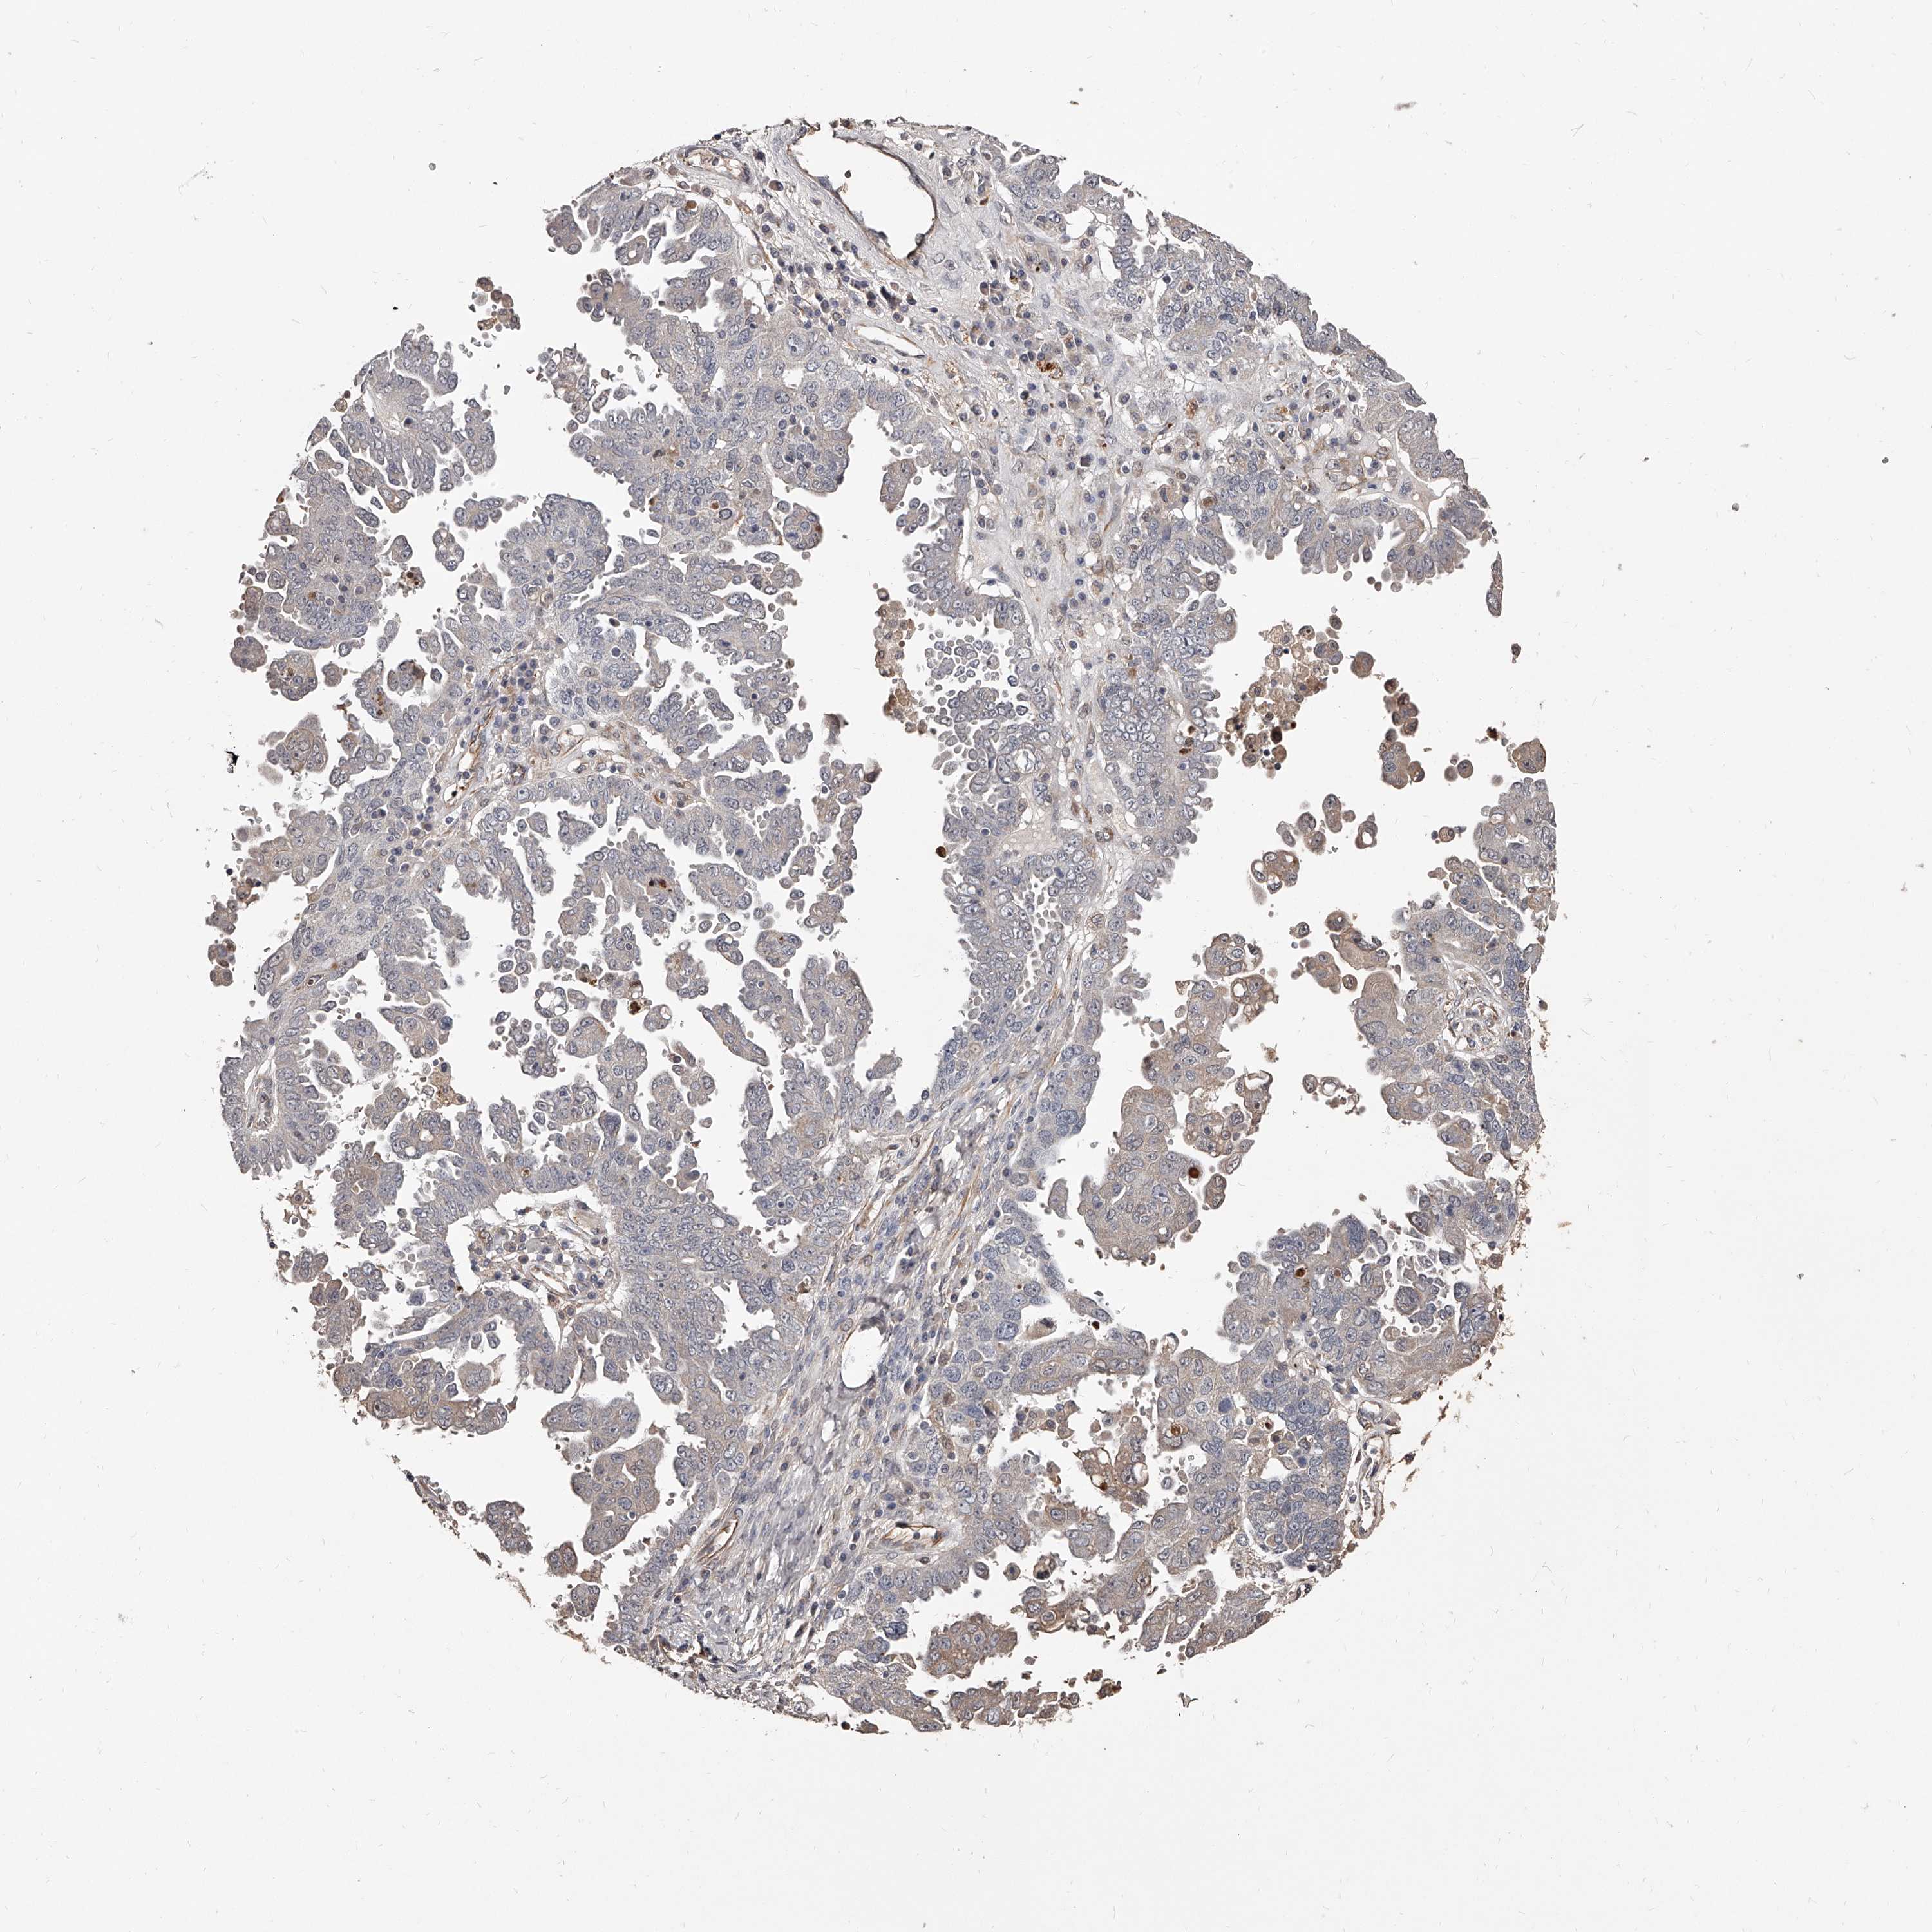

OVARIAN CANCER - Protein expressioni

A mouse-over function shows sample information and annotation data. Click on an image to view it in a full screen mode. Samples can be filtered based on level of antibody staining by selecting one or several of the following categories: high, medium, low and not detected. The assay and annotation is described here.

Note that samples used for immunohistochemistry by the Human Protein Atlas do not correspond to samples in the TCGA dataset.

Antibody stainingi

Antibody staining in the annotated cell types in the current human tissue is reported as not detected, low, medium, or high, based on conventional immunohistochemistry profiling in selected tissues. This score is based on the combination of the staining intensity and fraction of stained cells.

Each image is clickable and will lead to virtual microscopy that enables deeper exploration of all samples and also displays staining intensity scores, fraction scores and subcellular localization as well as patient and tissue information for each sample.

Antibody HPA019879

Antibody HPA020134

Antibody HPA029468

Cystadenocarcinoma, serous, NOS

Carcinoma, endometroid

Cystadenocarcinoma, mucinous, NOS

Carcinoma, NOS